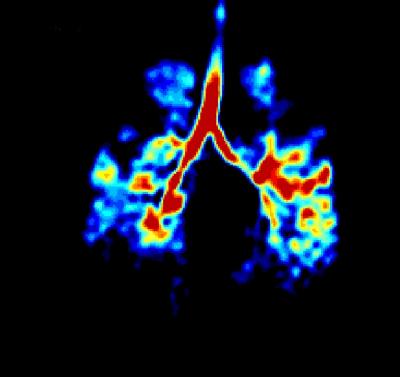

Researchers at the University of Sheffield have developed innovative technology which illuminates a person’s lungs and helps clinicians identify if they are functioning correctly. The new technology could result in earlier diagnosis of emphysema and smoking related damage, as well as other lung conditions and diseases.

The technique developed at Sheffield involves a person inhaling small amounts of harmless hyperpolarised (HP) noble gases (Helium-3 and Xenon-129), which are then imaged inside an MRI scanner. The gases are hyperpolarised using high power lasers by a process called optical pumping. The high resolution images of the airspaces that are produced offer additional functional information that is currently not available with traditional X-rays and lung CT scans.

Images obtained of lungs so far are shedding new light on a variety of different lung conditions and diseases. Tests carried out on smokers, for example, have shown signs of early emphysema.